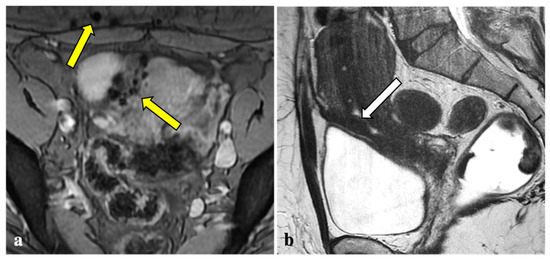

3.2. MRI Findings